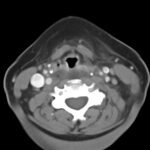

Retropharyngeal abscess (RPA) is an uncommon yet potentially life-threatening condition that is more often seen in young children and may be misdiagnosed in adults presenting with atypical features.1 Retropharyngeal abscess results from spread of antecedent upper respiratory tract infection or traumatic inoculation via foreign body ingestion or medical instrumentation. Clinically, RPA may present with fever, pharyngitis, neck pain, and dysphagia. Diagnosis is often confirmed with imaging studies. We present a case of a 66-year-old female with asthma, hypertension, and gastroesophageal reflux disease (GERD) who presented to the emergency department (ED) for evaluation of neck fullness, shoulder pain, dysphagia, and abdominal pain starting less than 24 hours prior to presentation. Computed tomography (CT) revealed a prevertebral/retropharyngeal fluid collection from the odontoid tip to the C4 vertebral body measuring 5.4 x 1.0 x 3.3 centimeters (cm) in size with associated edema at the left neck base extending into the upper chest, suggestive of retropharyngeal abscess. The patient received intravenous (IV) vancomycin and piperacillin/tazobactam and was transferred to a higher level of care for otolaryngologist evaluation. The patient remained stable without airway compromise while in our department. This case underscores challenges in diagnosing atypical presentations of RPA in adults, emphasizing timely recognition to prevent complications.